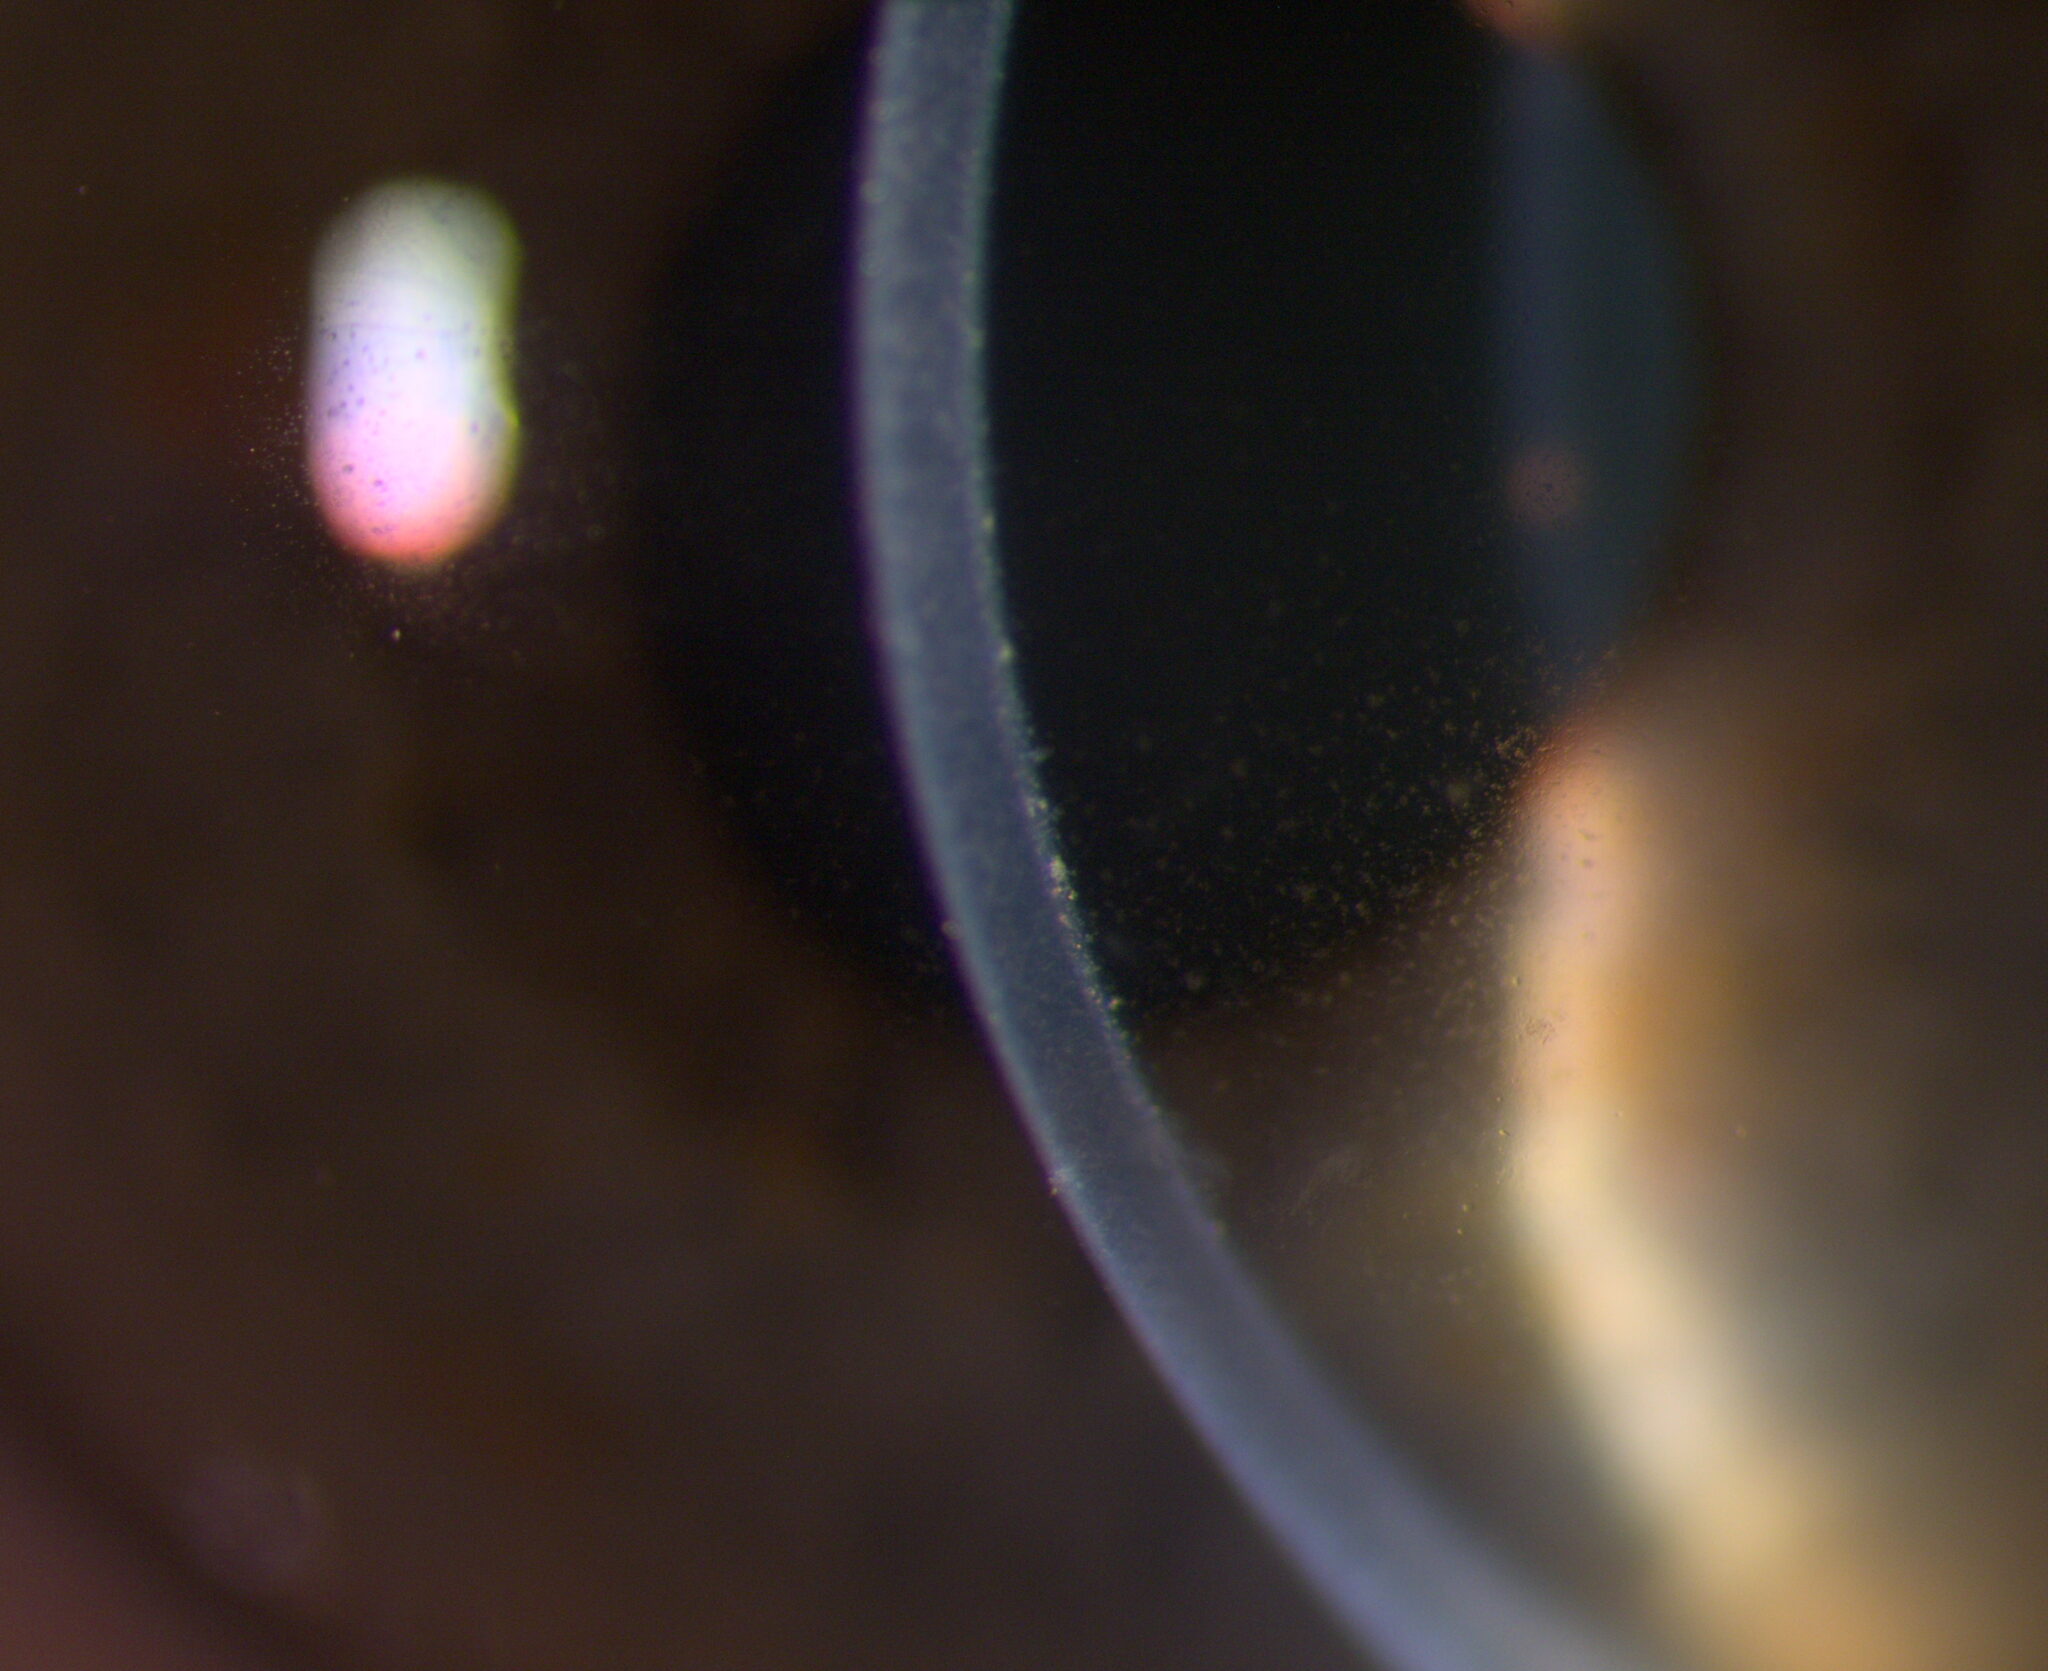

Break free from the ordinary and embrace the remarkable. Elara 900 redefines what’s possible in slit lamp microscopy. Combining legendary Haag-Streit Swiss-made optics with the revolutionary “P-Type” illumination and a dual integrated camera for an immersive 3D* experience: see with confidence across all parts of the eye.

Built to withstand the most demanding slit lamp microscopy, Elara 900 is designed to provide outstanding optical performance, ensuring you can detect subtle ocular changes with ease. Featuring legendary Haag-Streit optics – your guarantee for high light transmission and optical excellence – all optics undergo rigorous inspections to ensure unrivaled quality.

Unlike modular microscopes, where interchangeable components must be balanced, Elara 900’s key elements are optimized during the production process then seamlessly aligned into a single optical system. From lenses to illumination: the result is a clinical view you can trust.

Whether assessing the anterior or posterior segment or working under unfavorable light conditions – benefit from a view that is both natural and high in contrast. Elara 900’s Galilean microscope – with its five-step magnification range from 6.3x up to 40x – unveils more detail with every turn.

Elara 900’s revolutionary projector light source (“P-Type”) can emit colors across the entire visible spectrum, allowing different color temperatures to be selected for individual pathologies. Offering more illumination modes than traditional LED or halogen sources, the result is a high-resolution, high-contrast examination that aids in the identification of ocular structures. Infrared* illumination enables seamless Meibomian gland assessment, further boosting your workflow.